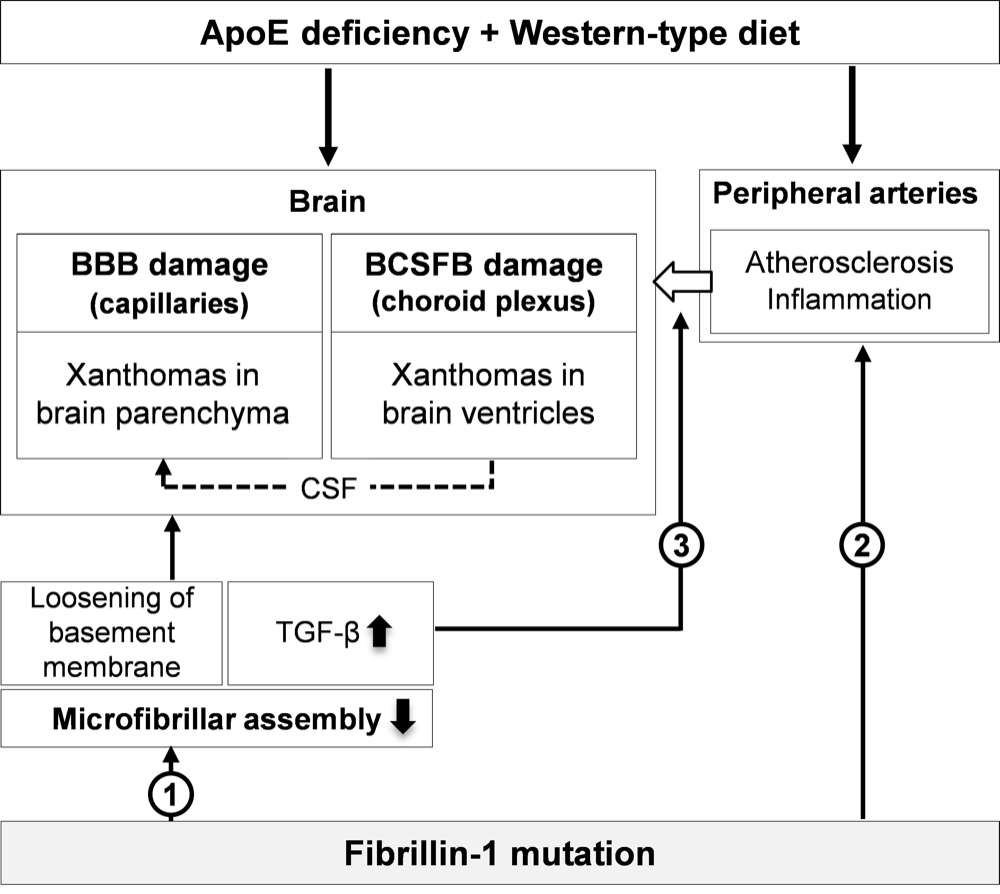

Chapter 4 Figure 9Mechanism of accelerated xanthoma formation in the brain of ApoE-/-Fbn1C1039G+/- mice. The ApoE-/- background together with a WD initiates BBB and BCSFB degradation. The BBB damage at the level of the capillaries and the BCSFB damage at the choroid plexus facilitate the entry of leukocytes and lipoproteins in the brain, promoting the development of xanthomas in the brain parenchyma and brain ventricles, respectively. The fibrillin-1 mutation potentiates xanthoma formation at three different levels: (1) by causing a decreased assembly of the microfibrils in the basement membrane, making it more loose, (2) by accelerating peripheral inflammation (atherosclerosis), stimulating the entry of leukocytes in the brain and (3) by increasing the (local) expression of the inflammation regulator TGF-β, promoting local inflammation and matrix degradation. In addition, due to the severe damage of the choroid plexus in ApoE-/-Fbn1C1039G+/- mice, CSF may be enriched with lipoproteins and activated leukocytes, leading to xanthoma formation in the parenchyma of e.g. the olfactory bulb, brain stem and cerebellum (dashed line).